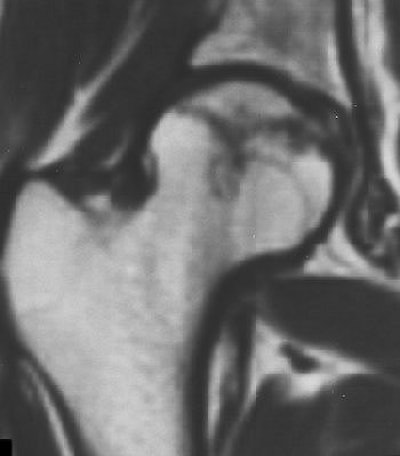

![]() |

| Coronal T1-weighted MR image, obtained six months after A-B and one week after onset of hip pain, shows diffusely decreased signal intensity (D). T1-weighted fat-saturated contrast-enhanced image shows nonenhancing lesion in subchondral area of femoral head surrounded by brightly enhanced marrow in the head and neck (G). Iida S, Harada Y, Shimizu K, Sakamoto M, Ikenoue S, Akita T, Kitahara H, Moriya H, "Correlation Between Bone Marrow Edema and Collapse of the Femoral Head," (AJR 2000, 174: 735-743). |

Iida's group explained that bone marrow edema should be considered a marker for a progressive illness. Its presence can delineate transient osteonecrosis -- a self-limited disease that can be resolved with treatment -- and osteonecrosis, which can progress to destructive arthrosis.